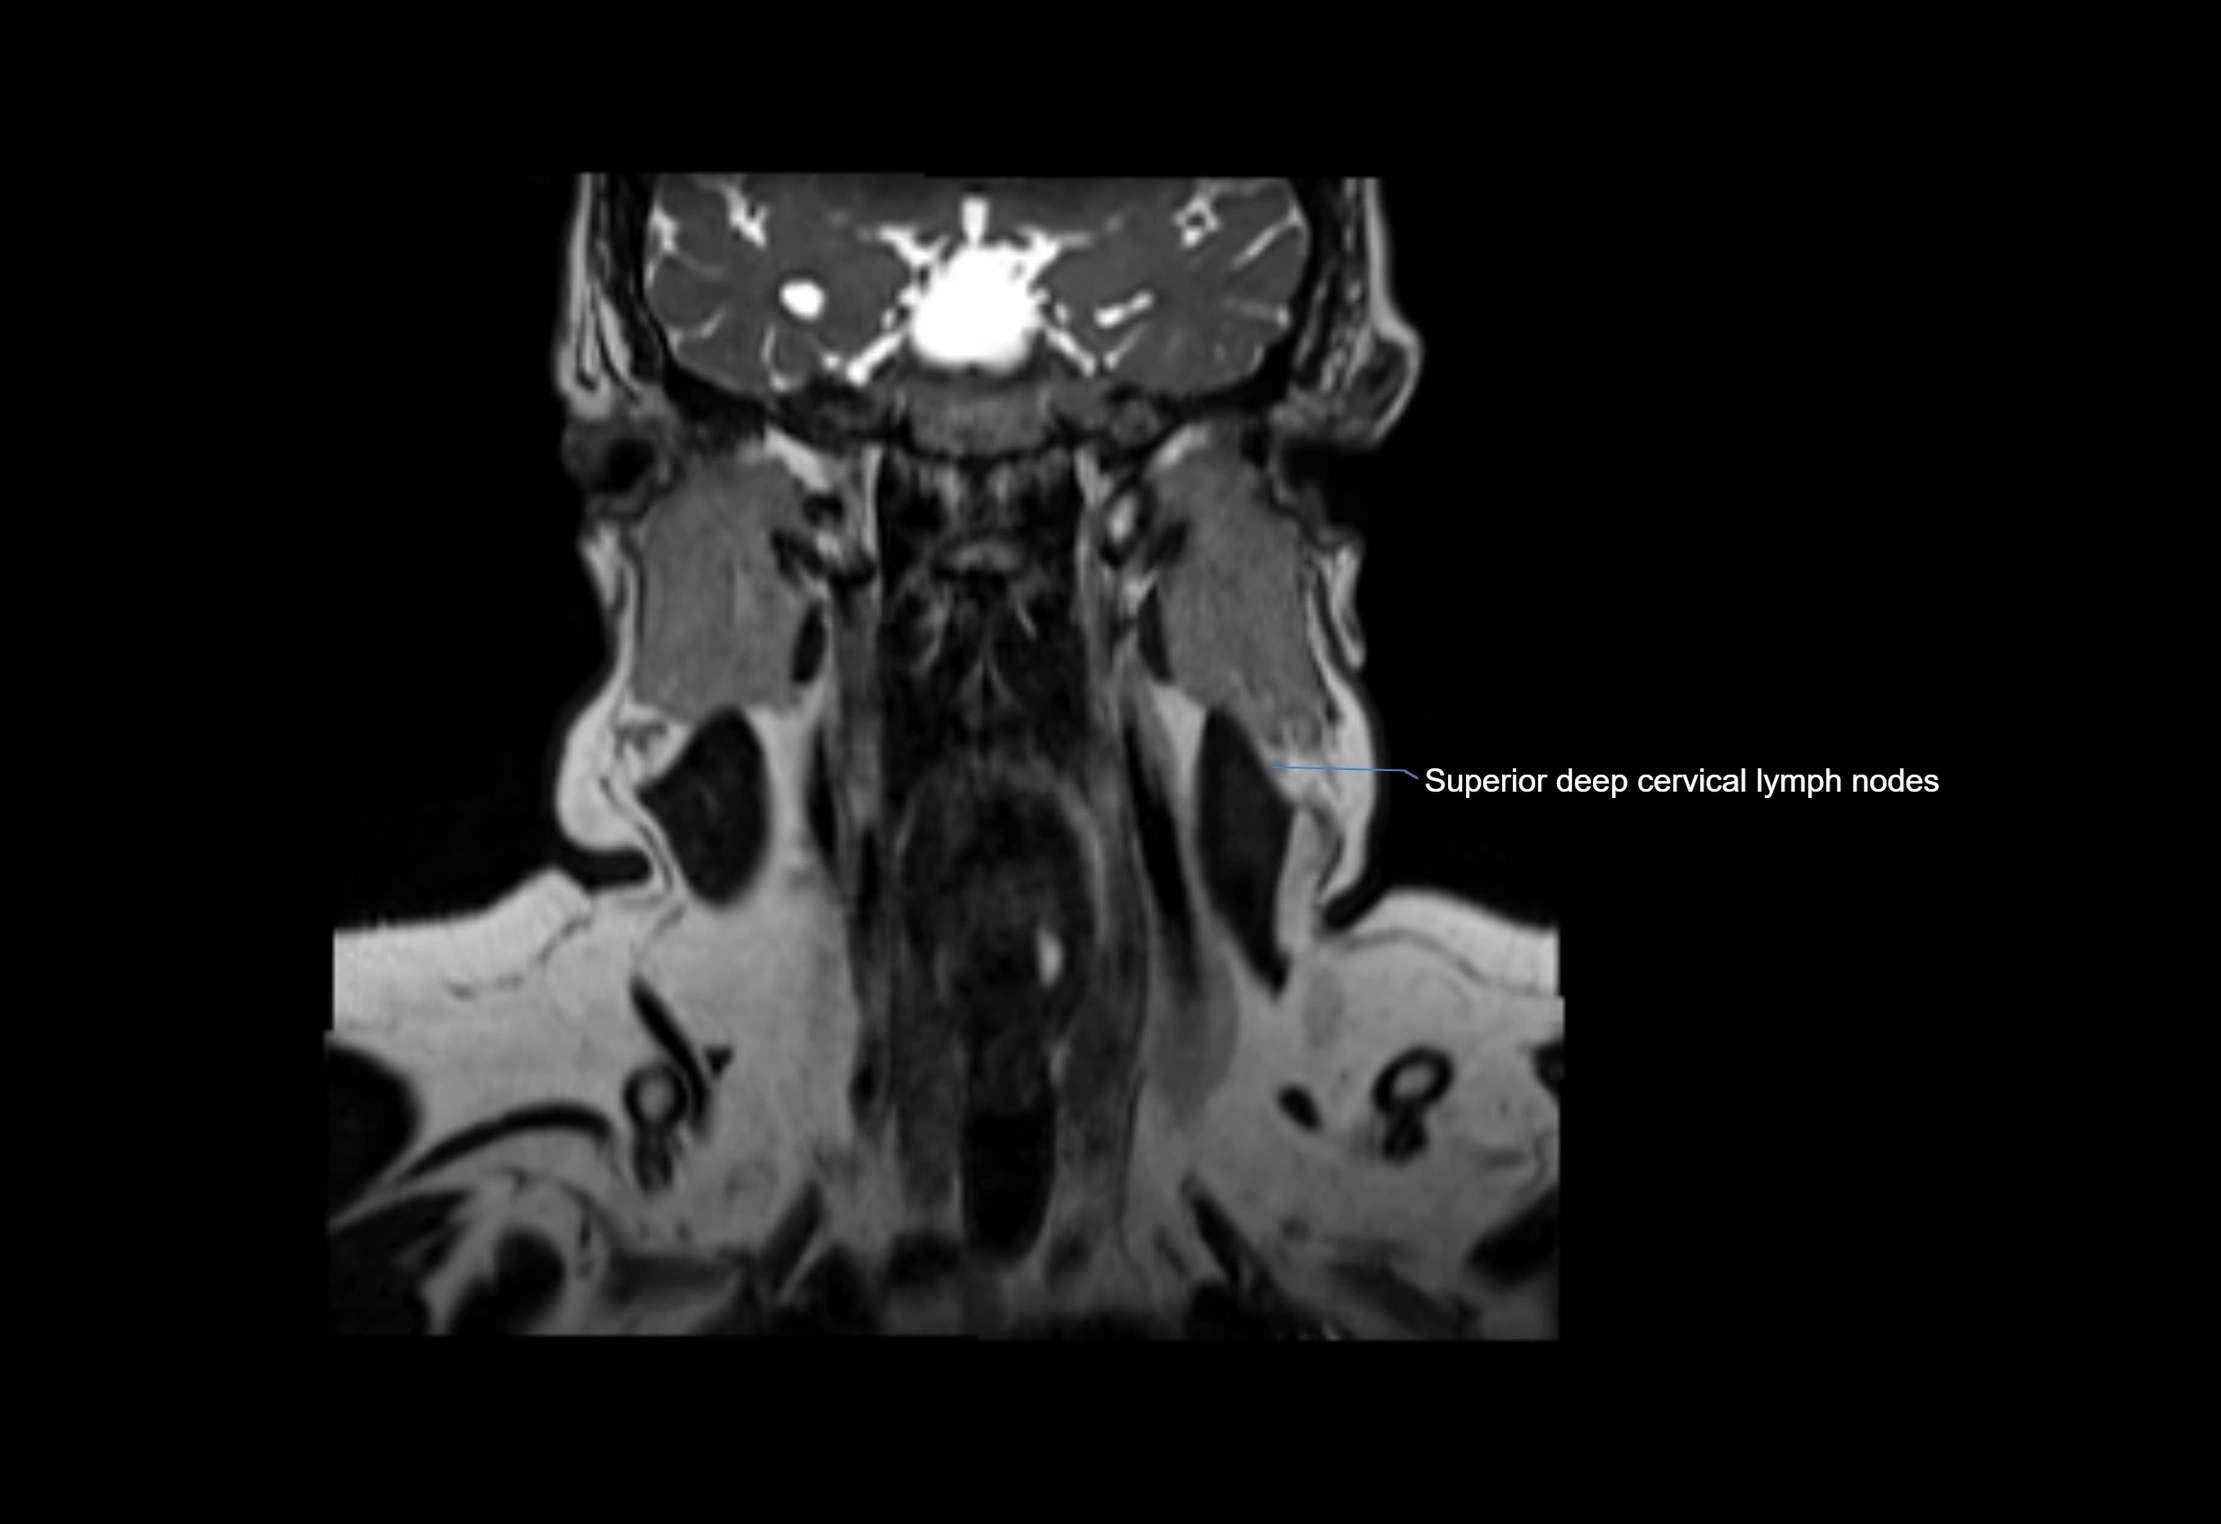

Location

• Found along primary lymph node chains, including preauricular, submandibular, parotid, and occipital regions

• Embedded in subcutaneous fat or superficial fascia, often lateral or posterior to primary nodes

• Variable in number; may occur unilaterally or bilaterally, depending on individual anatomy

MRI Appearance

T1-weighted images:

• Normal accessory nodes appear as small, oval hypointense to intermediate signal structures within subcutaneous fat

• Surrounded by hyperintense fat, enhancing contrast for visualization

• Pathological nodes may appear enlarged or rounded, sometimes with cortical thickening